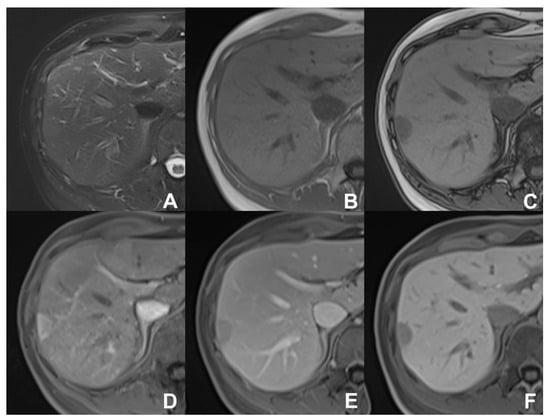

| GRE T1 3D DYNAMIC | AXIAL | PRE-ART 25″-PORTAL 70″-LATE 180″ | YES (if the lesion is hypervascular) | Benign hypervascular hepatocitic lesions appear hyperintense in HBP | |

| GRE T1 3D DYNAMIC | AXIAL | PRE-ART 25″-PORTAL 70″-LATE 180″ | YES (if the lesion shows atypical enhancement) | Hypointensity in HBP suspicious for HCC | |

| GRE T1 3D DYNAMIC | AXIAL | PRE-ART 25″-PORTAL 70″-LATE 180″ | YES | HBP increases the sensitivity of metastases detection | |